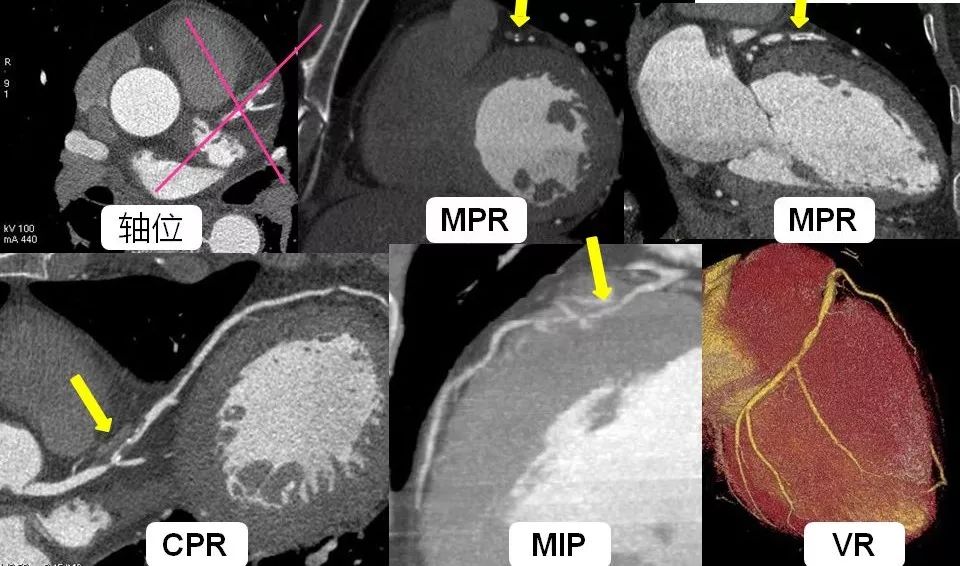

心脏磁共振成像( cardiac magnetic resonance,CMR)因其高组织分辨率、无电离辐射,在 CVD 精准诊断中发挥重要作用。本期心血管影像学评估专题相关研究中,均进一步证实CMR在多种CVD中的临床价值。然而,CMR 在临床实践中的推广仍然面临挑战,主要包括成本高、检查时间长、对设备及操作人员要求较高,且结果分析需要专业医师的解读等。AI 技术的引入显著推动了 CMR 在成像速度和多参数分析方面的进步。传统 CMR 检查通常需要较长的扫描时间,限制了其在急性期患者中的应用。各设备生产厂家使用基于卷积神经网络技术进行图像的重建去噪,从而可在更短时间里实现更高质量图像的采集。目前,所有图像后处理软件均已引用该技术以实现多种序列上心脏腔室结构的自动分割,使图像分析过程得到大大简化。这些技术在保证图像质量的前提下,显著缩短扫描时间,使高分辨率 CMR 检查在数分钟内得以完成。此外,基于深度学习的 CMR 新技术允许患者在不屏气情况下进行图像采集,这不仅大大提升患者耐受性,还进一步提高其在临床环境中的可行性。